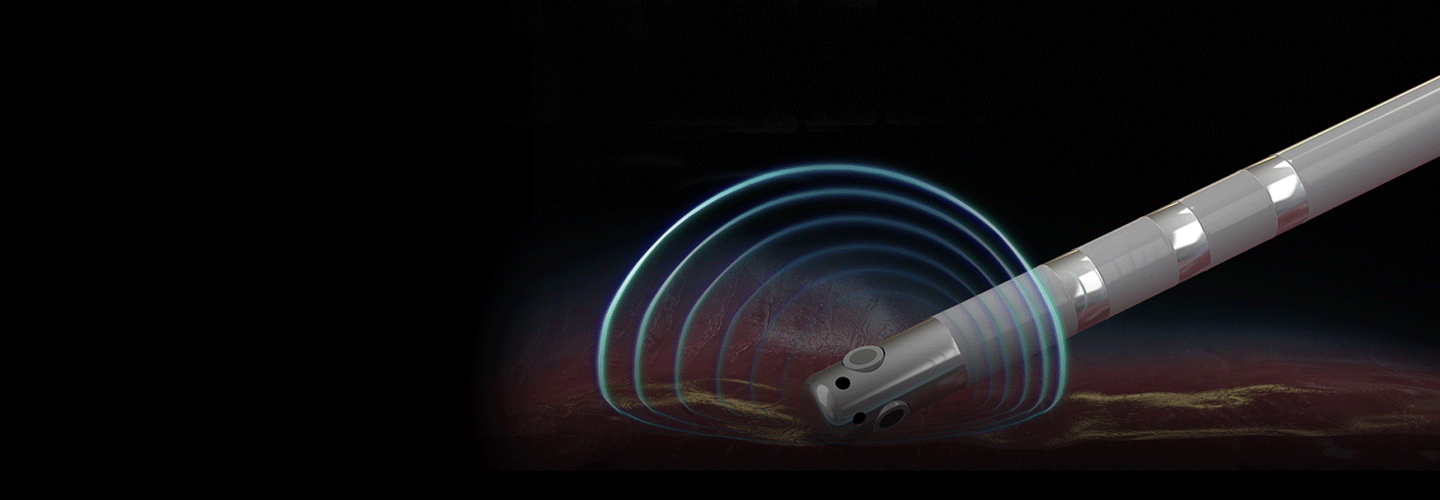

DIRECTSENSE™ Technology

Available exclusively on the RHYTHMIA HDx™ Mapping System, DIRECTSENSE™ Technology features a unique local impedance measure that reveals powerful insights into tissue resistivity and subsurface heating.

INTELLAMAP ORION™ Mapping Catheter

Designed to work with the RHYTHMIA™ HDx Cardiac Mapping System, INTELLAMAP ORION supports HD mapping, providing unprecedented clarity in a range of cases—from simple to the most complex.